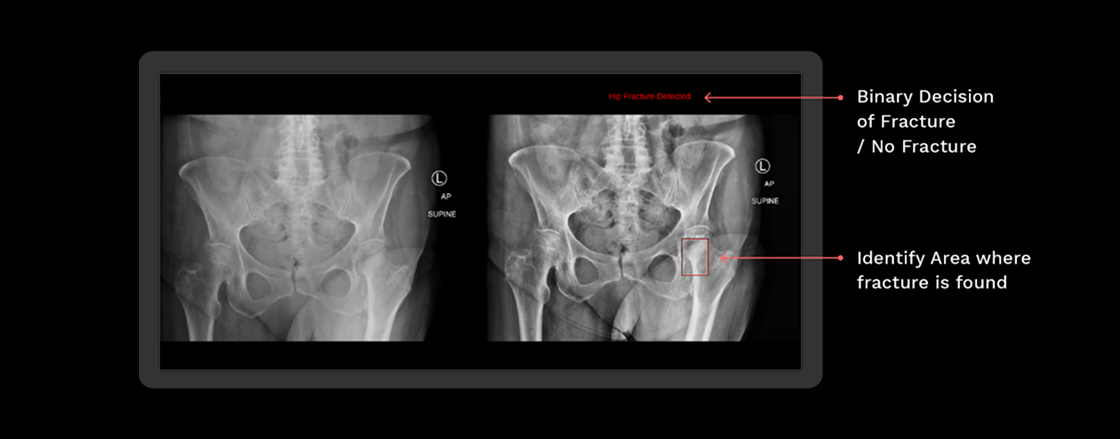

Rbfracture™

AI-powered, automatic detection of trauma-related findings

Benefits of using RBfracture™

Supports trauma

reads 24/7

Improved diagnostic

accuracy

Suggested diagnosis

within seconds

Trial showing improved diagnostic accuracy for Emergency Care residents when

reviewing hip fracture X-rays

Above shows the change using RBfracture™ has had on reviewing hip fracture images by reader group